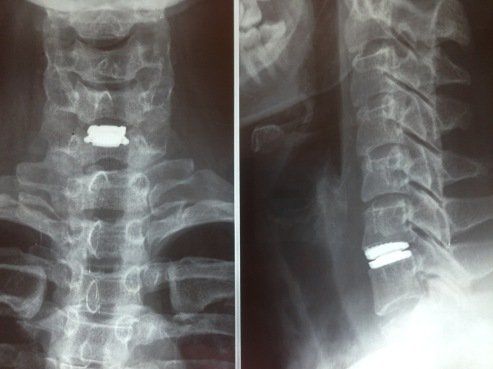

تم تصميم الأطراف الاصطناعية للقرص لتحل محل الأقراص التالفة. يحاولون الحفاظ على حركة الجزء المصاب بمجرد إزالة القرص نتيجة للانزلاق الغضروفي. تتمثل إحدى مشاكل إزالة القرص واستبداله بالطعم في فقدان حركة الجزء المعالج ، مما يؤدي إلى زيادة التحميل على المستويات المجاورة ، مما يسرع من انحطاطه.